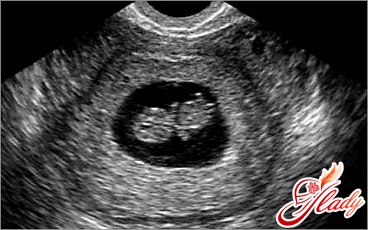

Беременность 6 неделя узи: Хороший ультразвуковой сканер на этом этапе беременности может уже уловить сокращение бьющегося в крошечном теле сердечка. В это же время начинают формироваться отдельные части гортани и внутреннего уха, появляются зачатки ручек и ножек. Кроме того, стремительными темпами начинают развиваться конечности и зачатки мозга. Головка постепенно начинает принимать знакомые очертания, на данном этапе у плода формируются внутренние органы (легкие, печень и пр.), появляются глазки и ушки. Именно в этот период беременности начинает интенсивно развиваться плацента.

Если у вас беременность 6 неделя, то на этом сроке длина зародыша от темени до крестца составляет от 2 до 4 мм. Объем околоплодной жидкости — около 2-3 мл.